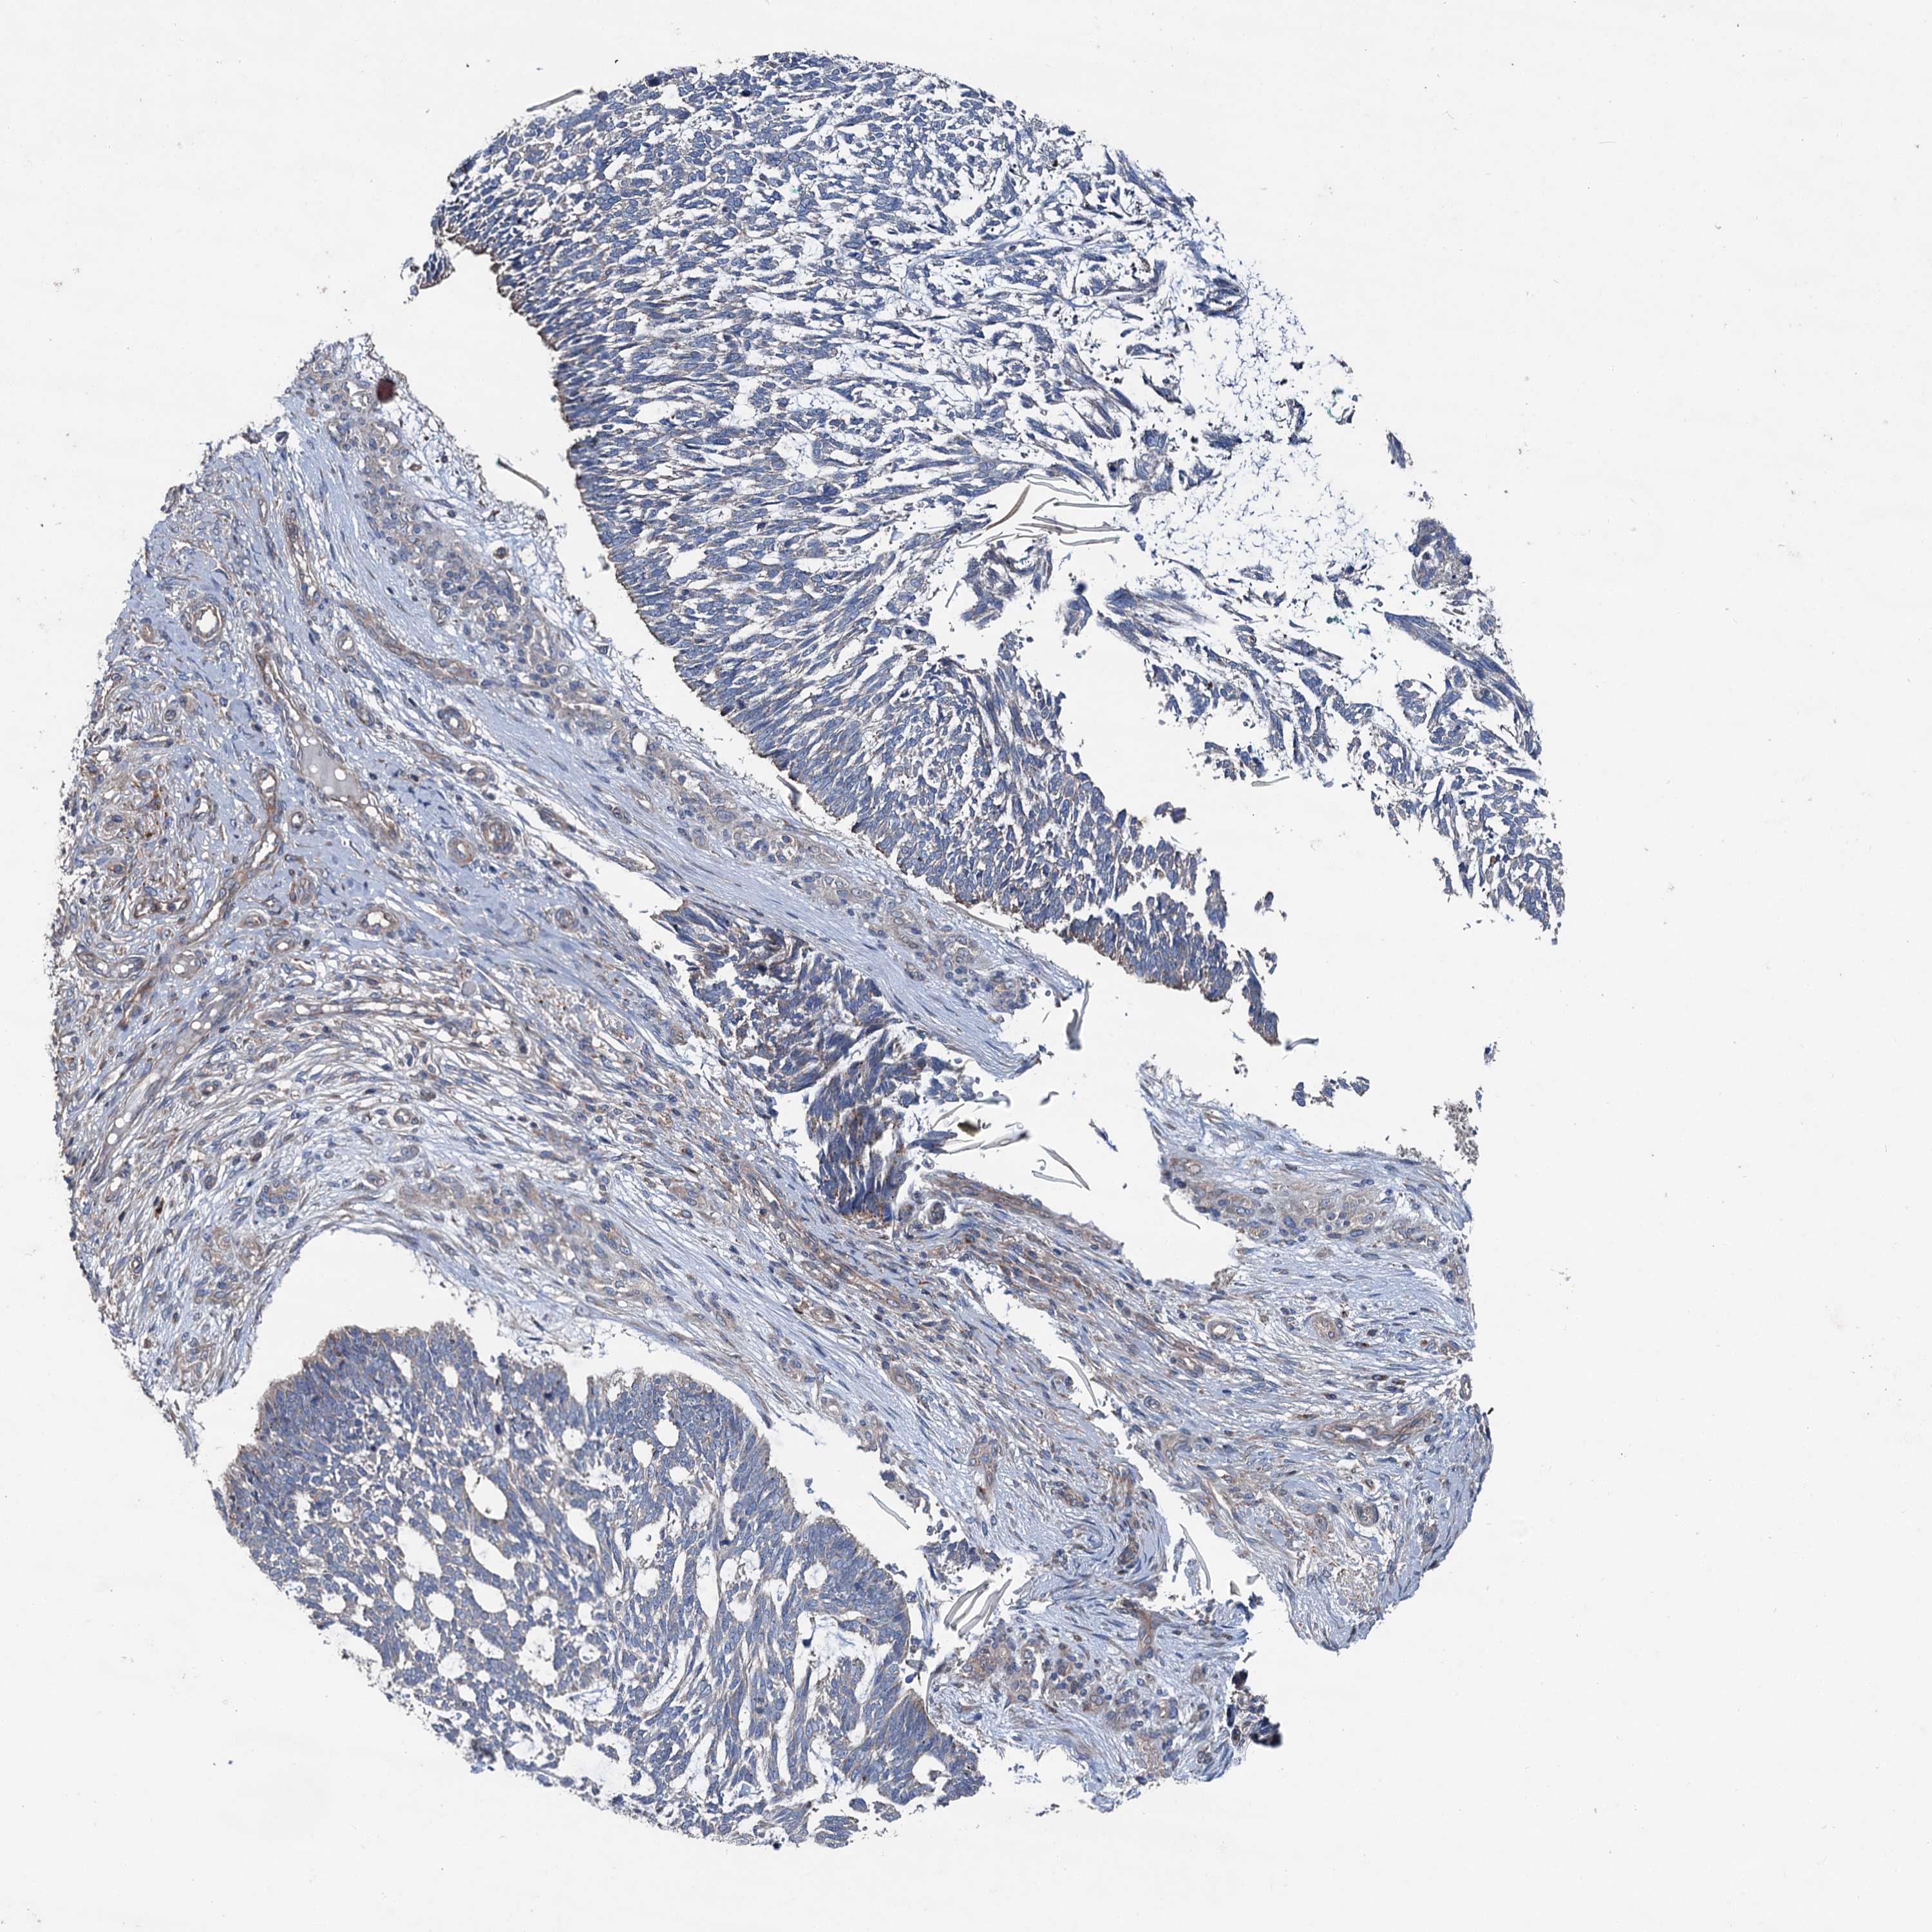

SKIN CANCER - Protein expressioni

A mouse-over function shows sample information and annotation data. Click on an image to view it in a full screen mode. Samples can be filtered based on level of antibody staining by selecting one or several of the following categories: high, medium, low and not detected. The assay and annotation is described here.

Antibody stainingi

Antibody staining in the annotated cell types in the current human tissue is reported as not detected, low, medium, or high, based on conventional immunohistochemistry profiling in selected tissues. This score is based on the combination of the staining intensity and fraction of stained cells.

Each image is clickable and will lead to virtual microscopy that enables deeper exploration of all samples and also displays staining intensity scores, fraction scores and subcellular localization as well as patient and tissue information for each sample.

Antibody HPA038804

Squamous cell carcinoma, metastatic, NOS

Squamous cell carcinoma, NOS